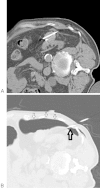

Although percutaneous ablation of small renal masses is generally safe, interventional radiologists should be aware of the various complications that may arise from the procedure. Renal hemorrhage is the most common significant complication. Additional less common but serious complications include injury to or stenosis of the ureter or ureteropelvic junction, infection/abscess, sensory or motor nerve injury, pneumothorax, needle tract seeding, and skin burn. Most complications may be treated conservatively or with minimal therapy. Several techniques are available to minimize the risk of these complications, and patients should be appropriately monitored for early detection of complications. In the event of a serious complication, prompt treatment should be provided. This article reviews the most common and most important complications associated with percutaneous ablation of small renal masses.